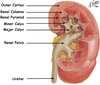

what are the 3 regions of the kidney

The cortex- contains nephrons, medulla- and pelvis

In a nephron, which 3 structures are in the cortex and which 3 are in the medulla

The structures that are contained within the cortex are (left side of image);

Renal Corpuscle (glomerular tuft, bowmen’s space and bowman’s capsule)

Post convoluted Tubules

Distal convoluted Tubule

The structures that are contained within the medulla are (right side of image);

Loop of Henle

Collecting ducts

Vasa Recta